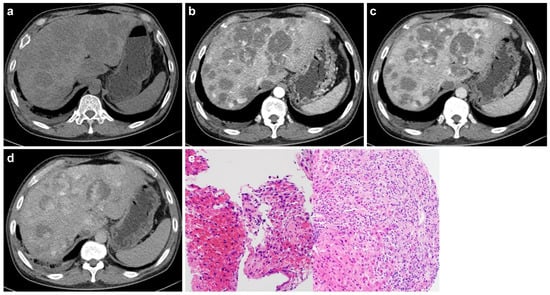

Primary Hepatic Angiosarcoma: Distinct Imaging Phenotypes Mirroring Histopathologic Growth Patterns in a Retrospective Human Study

Background/Objectives: To date, no studies have examined radiologic findings by histologic patterns of primary hepatic angiosarcoma; this study clarified radiologic findings of primary hepatic angiosarcoma according to distinct histologic patterns. Methods: From January 2010 to October 2024, 17 individuals (mean age, 69 years ± 11; 11 men) with pathologically confirmed primary hepatic angiosarcoma underwent computed tomography (CT) with or without magnetic resonance imaging (MRI). Histologic patterns were classified as mass-forming, subdivided into vasoformative and non-vasoformative (epithelioid and spindled) patterns, or non-mass-forming, subdivided into sinusoidal and peliotic patterns. Two radiologists independently reviewed CT and MRI images, classifying lesions as non-mass-forming or mass-forming. Hypervascular portions and targetoid patterns were also assessed. Associations between histologic patterns and radiologic findings were evaluated using Fisher’s exact test. Results: Mass-forming tumors were observed in 13 individuals (76.5%), and non-mass-forming tumors in 4 individuals (23.5%). Significant correlation (p < 0.05) was found between radiologic classification (non-mass-forming or mass-forming) and corresponding pathologic patterns. Pathologic subdivision into vasoformative and non-vasoformative patterns did not correlate with hypervascular portions on imaging. Conclusions: Pathological classification into mass-forming and non-mass-forming patterns corresponds closely to radiologic classification of mass-forming and non-mass-forming lesions, indicative of strong pathologic features in imaging. Full article

Show Figures

Figure 1